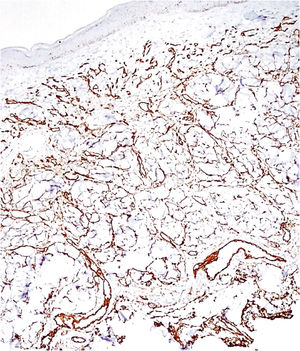

Histopathology revealed a rectified epidermis and proliferation of small vessels, more intense in the upper dermis, but extending to the middle dermis without cell atypia (Fig. 2). The immunohistochemical analysis showed positivity for CD31 (vascular endothelium), CD34 (vascular endothelium and dermal dendrocytes) and negativity for D2-40 and HHV-8 (Fig. 3).

Diffuse dermal angiomatosis of the breast (DDAB) is a poorly described entity that affects exclusively middle-aged, obese women with macromastia and who are smokers.1–3 Clinically, the lesions range from reticulated erythematous patches to indurated plaques surrounded by opaque erythema. Histopathological examination demonstrates endothelial cell proliferation between collagen fibers. Small vascular lumens constituted by spindle-shaped endothelial cells with vacuolated cytoplasm are formed throughout the dermis. This characteristic can be better demonstrated by the immunohistochemical markers CD31 and CD34 (endothelial cell markers).3 The histological differential diagnoses include acroangiodermatitis, Kaposi's sarcoma, low-grade angiosarcoma, and reactive angioendotheliomatosis. The negativity for HHV-8 rules out the possibility of Kaposi's sarcoma.